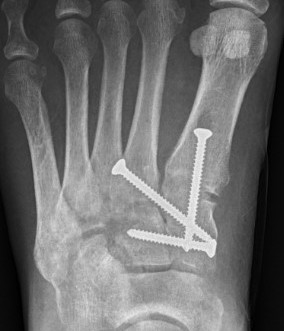

Screw fixation

AP view

- 1st metatarsal to medial cuneiform - screw

- 2nd metatarsal to intermediate cuneiform - screw

- medial cuneiform to base of second metatarsal - screw

+/- medial cuneiform to intermediate cuneiform - screw